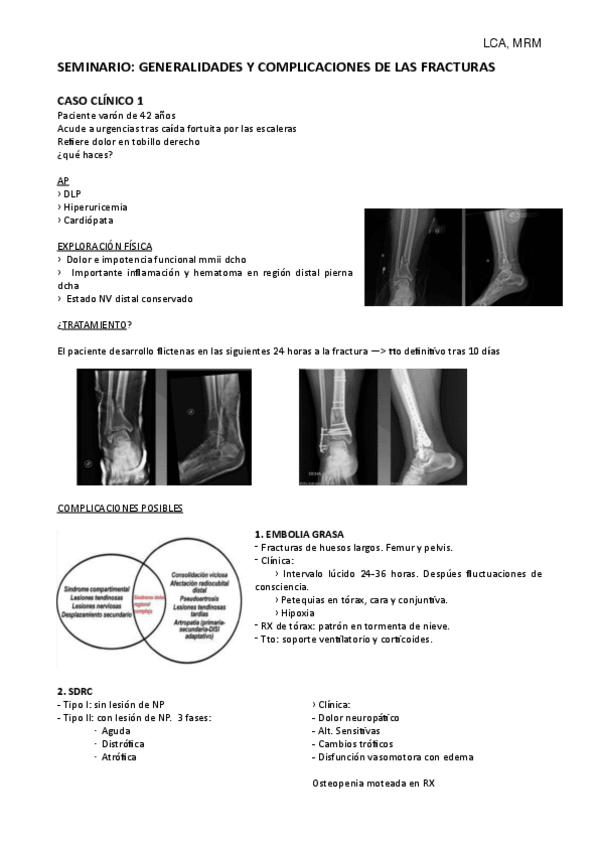

SEMINARIOS DE TRAUMATOLOGÍA

He publicado nuevos apuntes de 4º Enfermedades del Aparato Locomotor: SEMINARIOS DE TRAUMATOLOGÍA